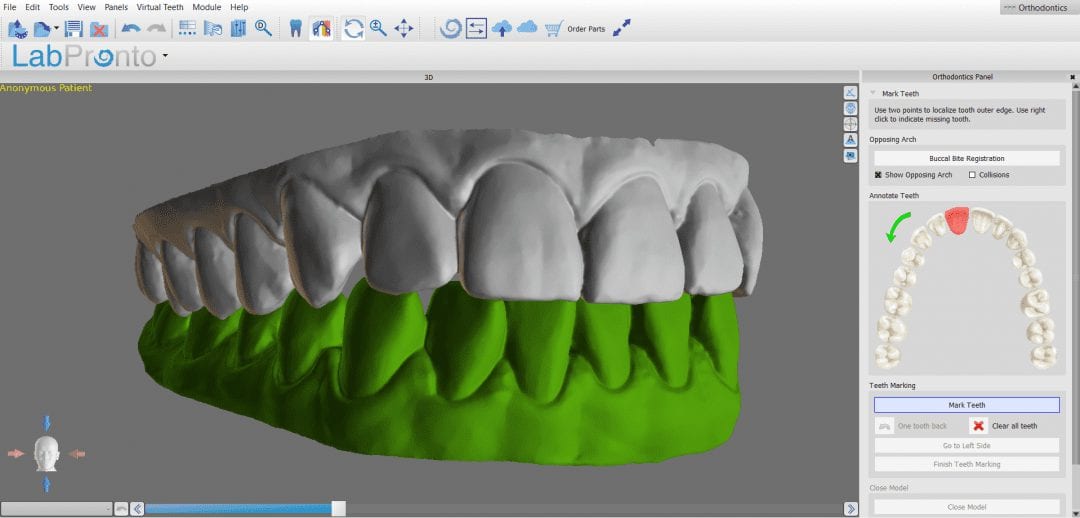

The data was then taken to BlueSkyBio’s Orthoplan for design

Once you are satisfied with the models and the correct occlusal scheme, you can export those models in STL, OBJ, or PLY formats and import them into a third party software. Here, we have them imported into BlueSKyBio Ortho Planning software. Download the case files and design along